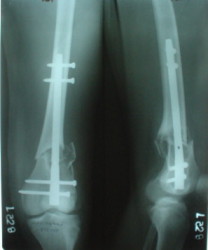

Отправитель: Alexander Chelnokov 27 Декабрь 2003, 21:34

Sorry but I've just prepared postop images - attached. A solid 13 mm nail was used. A few degrees of recurvation appears to be which i missed on image intensifier. I'm still uncertain about

advantages/disadvantages of ante/retrograde nailing for such fractures.

The fixation as you have done is excellent. The locking screws on either side of the # are so apart. When we put in a supracondylar nail thro a keyhole incison in the knee, the locking bolts will be nearer the # and will be more stable allowing him to bear wt early. That was the reason the supracondylar nail was innovated. The locking is done by jig and no freehand method saving time.